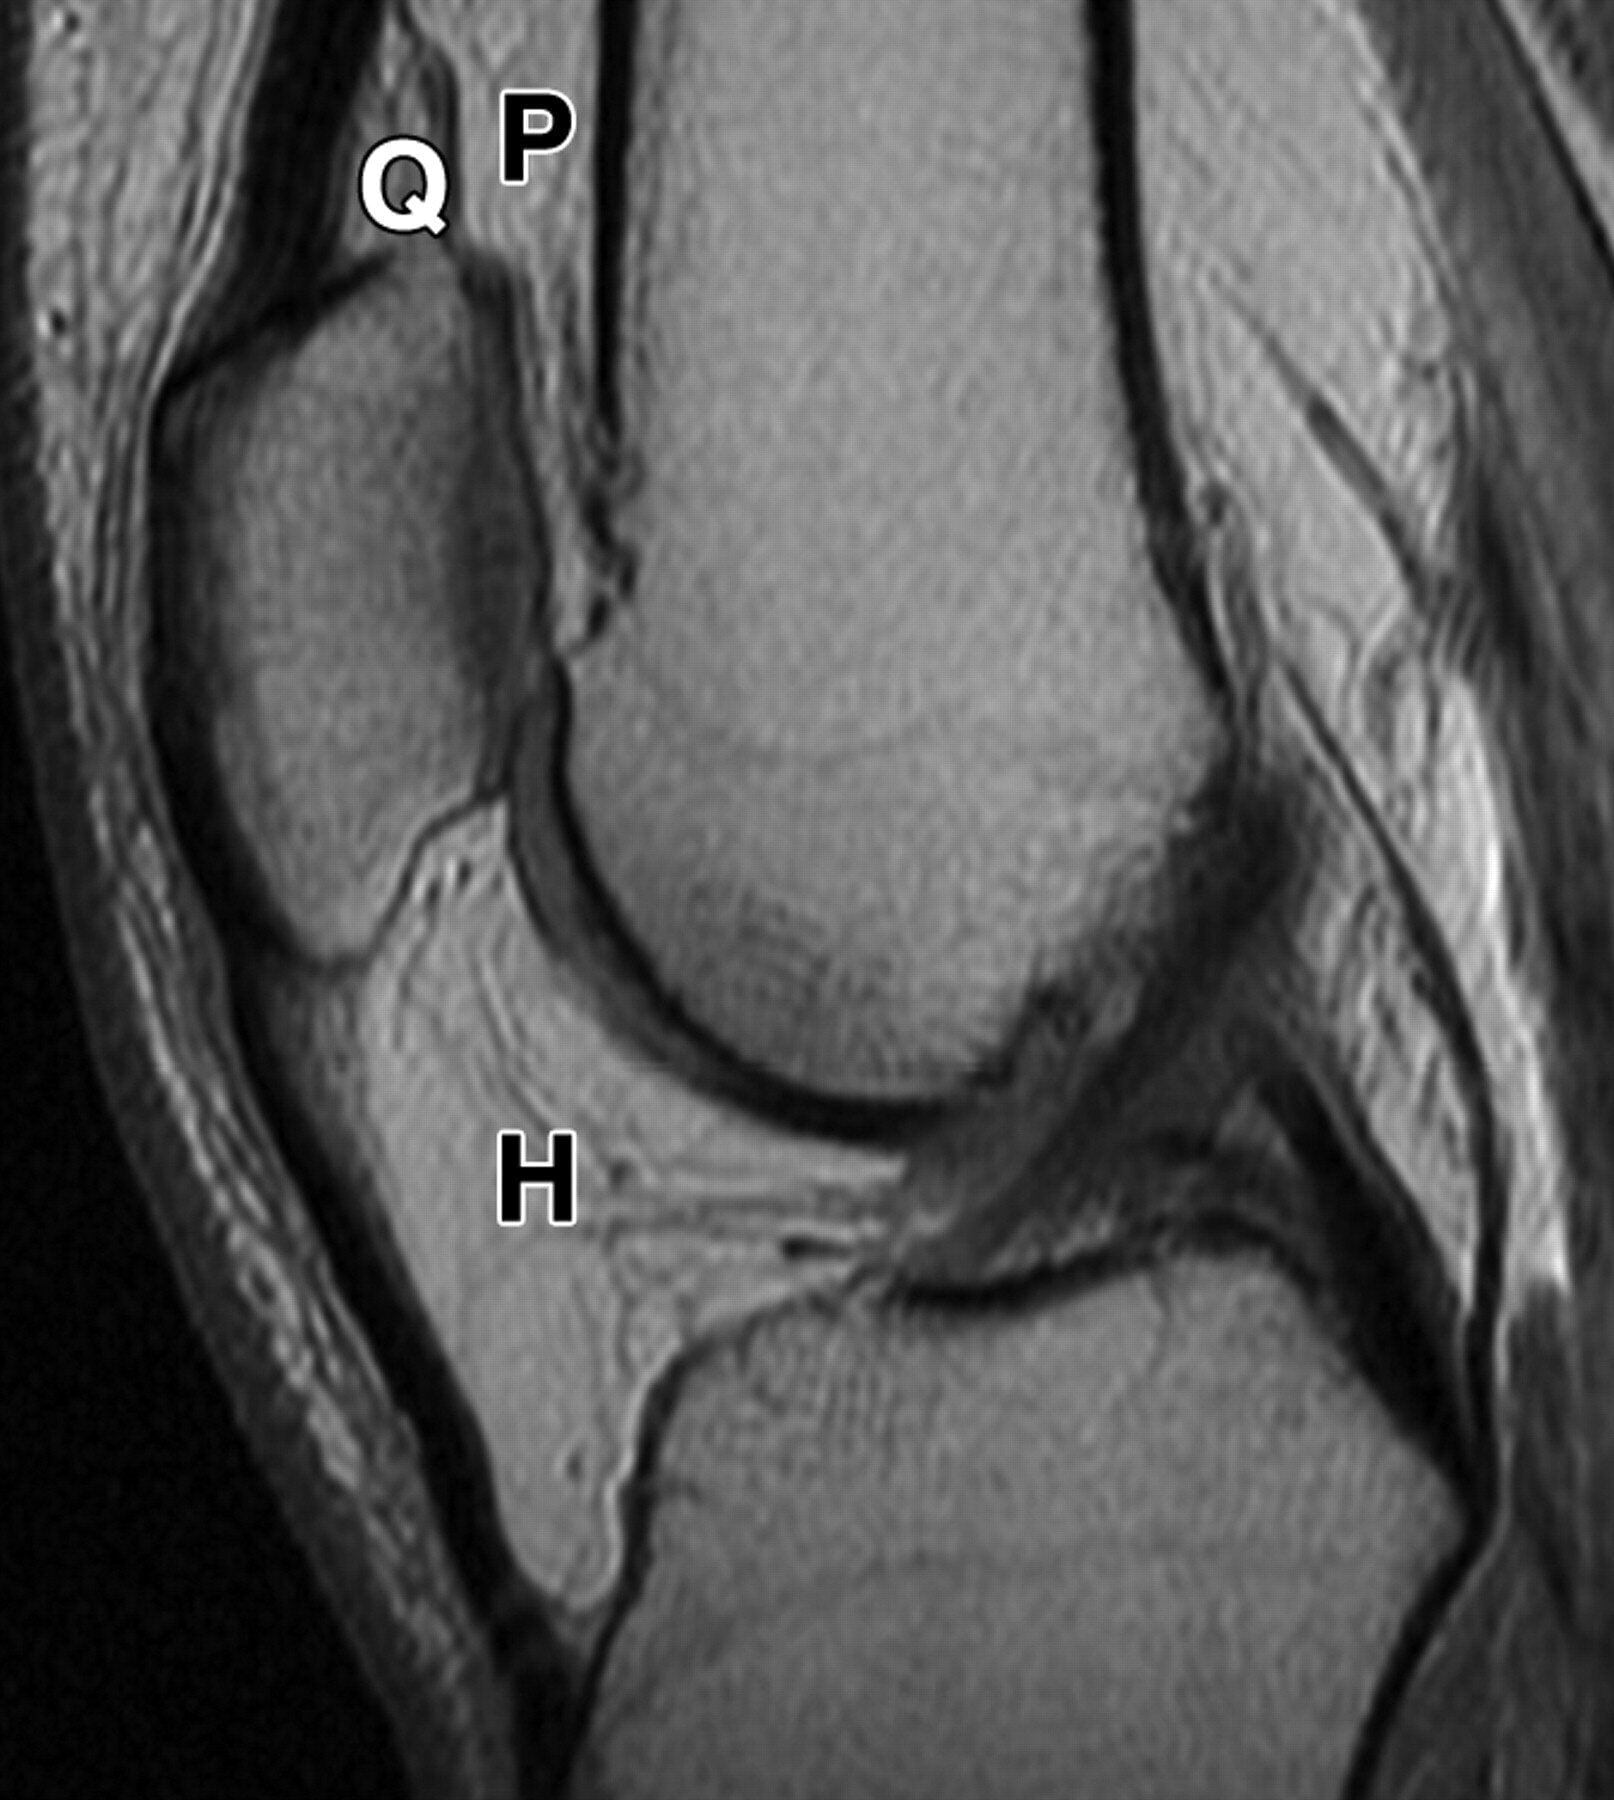

Knee Pain: Fat Pad Irritation or Hoffa’s Syndrome

Fat pad irritation (Hoffa’s syndrome) is a condition that falls under the broad umbrella...